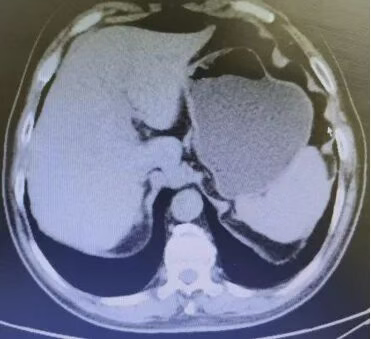

Abdominal CT films from August 13, 2019 (2 images)